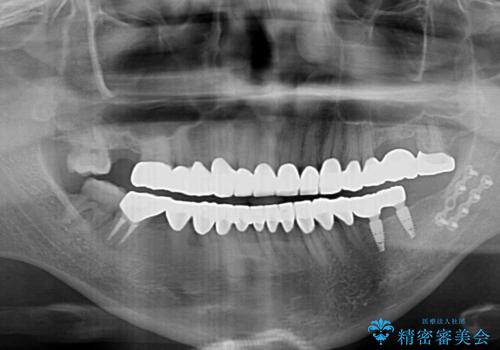

咬み合わせを改善するに当たって、抜歯しなければならない歯や歯列の改善が必要な箇所があったため、矯正治療やインプラント治療から始めていくこととしました。

不自然なくらい真っ白にしたいとのことでしたので、透明感のないフルジルコニアクラウンを用いて補綴することとしました。